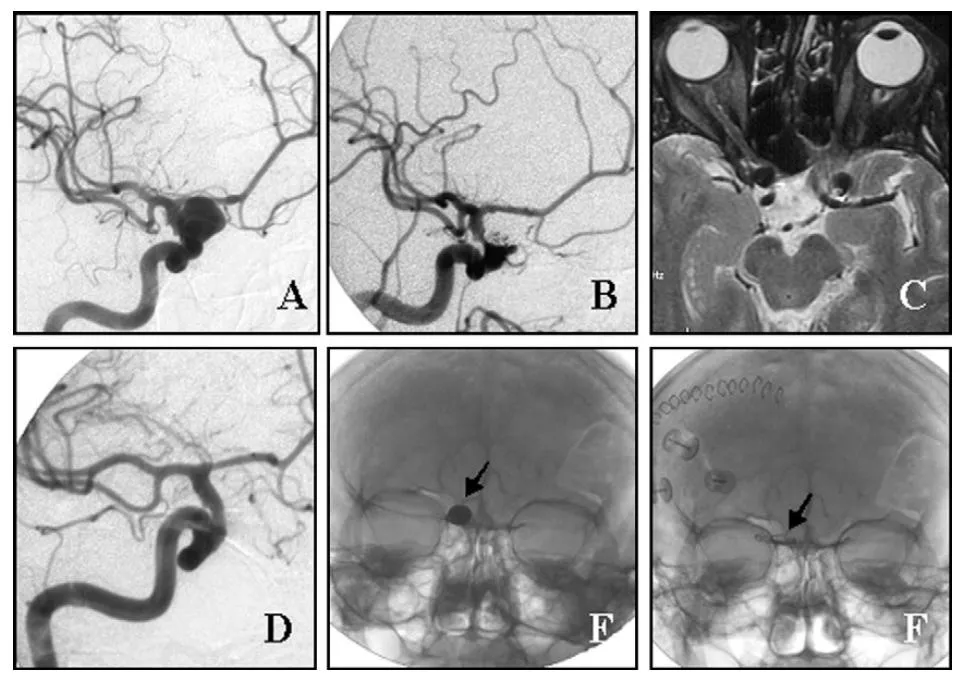

典型病例是一位61岁女性,右侧眼动脉动脉瘤栓塞术后两年,出现右眼视力下降和复视,MRI证实弹簧圈团块正在压迫右侧视神经。手术采用右侧翼点开颅联合硬膜外前床突磨除,临时阻断颈内动脉后切开瘤顶取出弹簧圈及伴随血栓,术后视力有所改善,但复视症状仍然持续。

(A)诊断性血管造影显示右侧眼动脉动脉瘤。

(B)栓塞术后22个月,患者出现右眼视力下降;弹簧圈栓塞术后2年血管造影显示动脉瘤闭塞率为90%。

(C)术前MRI显示弹簧圈团块压迫右侧视神经。

(D)术后血管造影显示动脉瘤完全闭塞。

E、F)术前与术后颅骨X线片,分别显示栓塞弹簧圈的位置与弹簧圈取出后动脉瘤夹的位置(箭头所示)。